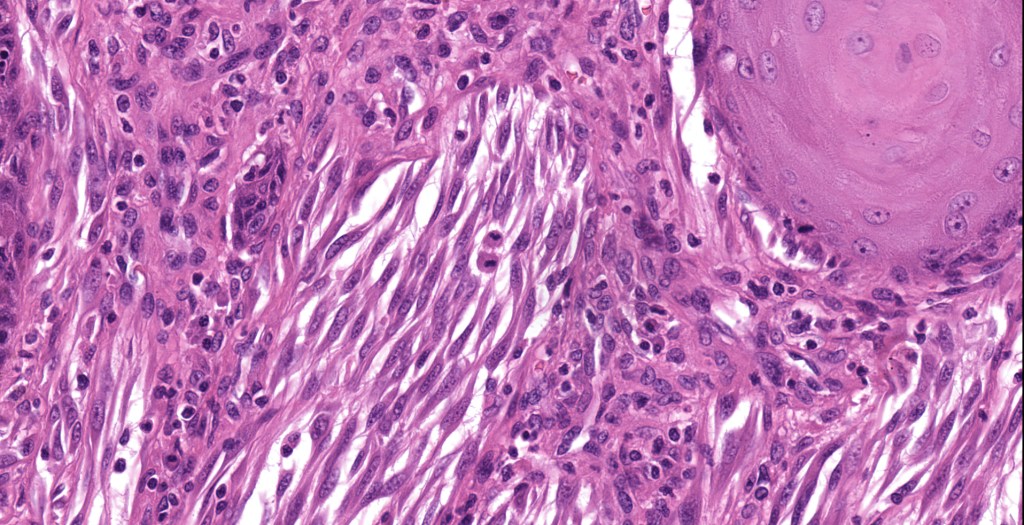

•Junctional nests often vertically orientated, dyscohesive with a surrounding retraction artifact

•Pleomorphism is almost invariable but affects all of the population to the same extent i.e., the cells & nuclei all look very much the same

•Spindle cell nests often display a “raining down” growth pattern

•Spindle cells have abundant cytoplasm and vesicular nuclei with small nucleoli

•Epithelioid cell variants often show greater pleomorphism and cells can frequently appear bizarre with abundant, sometimes ground glass cytoplasm and large vesicular nuclei with prominent eosinophilic nucleoli, multinucleate cells are often seen

•Intracytoplasmic pseudoinclusions commonly present in epithelioid cells

•Kamino bodies (often multiple) are a characteristic feature